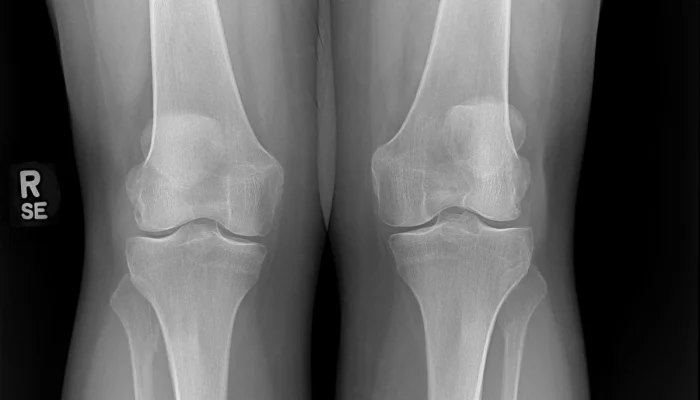

X-ray knees AP standing view

Diagnostic Imaging

A diagnosis of osteoarthritis is usually confirmed by x-ray before planning a joint injection.